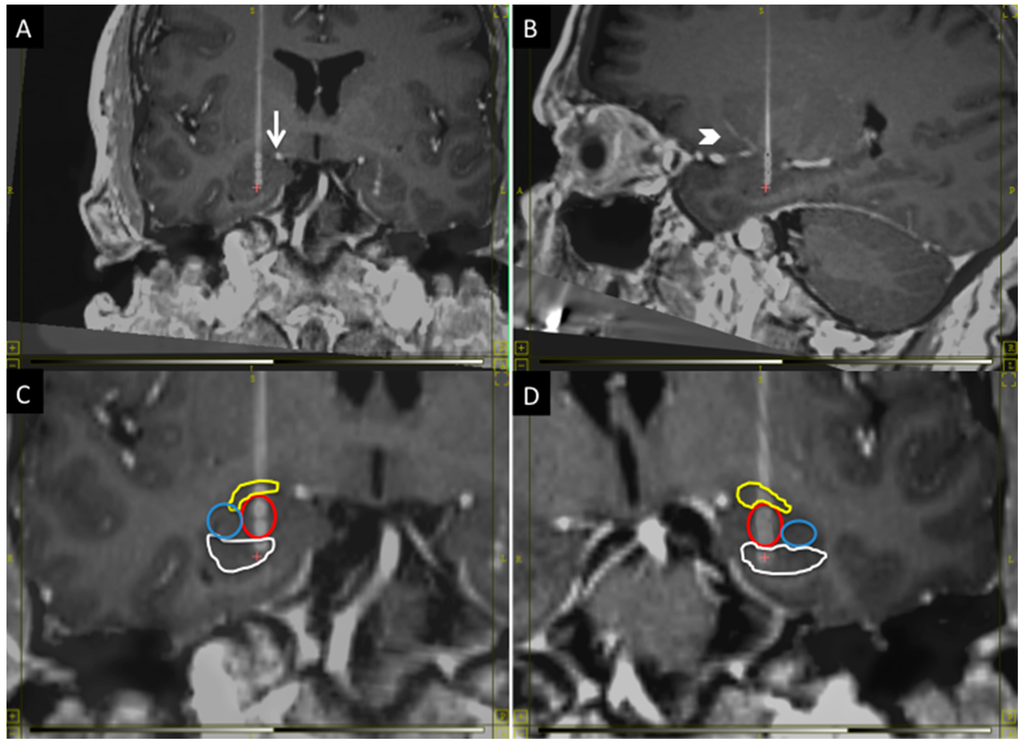

The BLn is located in the inferior portion of the amygdala. It is at the center of the amygdala where it is flanked laterally by the lateral nucleus and medially by the basomedial and basolateral ventromedial part [14]. The central and medial nuclei of the amygdala are dorsal to the BLn. When the MRI is oriented along the AC-PC plane, the fornices can be seen crossing the hypothalamus in the same coronal plane as the BLn within the amygdala [14]. Within this coronal plane, the BLn is located in the center of the amygdala from a medial-to-lateral perspective. When studying the axial plane at this level, the BLn is located just anterior to the tip of the temporal horn, which thus serves as another important landmark [11]. Finally, the inferior border of the BLn is marked by the presence of the head of the hippocampus (Figure 1).

Figure 1.

The figure shows the anatomical position of the BLn electrodes in the coronal plane (A,C,D) and sagittal plane (B): (A) The electrode must avoid the superior extent of the ambient cistern (arrow); (B) and the lenticulostriate vessels (arrowhead); (C,D) respectively show the right and left Bln electrodes with segmentation of the nuclei: in yellow, the central nucleus; in red, the basolateral nucleus; in blue, the lateral nucleus and, in white, the head of the hippocampus. The electrode contact distribution, from dorsal to ventral: Central nucleus (one contact); BLn (two contacts); Hippocampus (one contact). Laterally: Lateral nucleus (zero contacts).

The electrode trajectory must avoid critical structures to permit a safe transfrontal approach. It should be posterior to the lenticulostriate perforator vessels from the first segment of the middle cerebral artery and it should remain lateral to the superior aspect of the ambient cistern (Figure 1). Finally, the trajectory should be seen traversing just anterior to the tip of the temporal horn to confirm the location within the BLn [11]. The location of the entry point will vary depending on the anatomy of the critical structures. In general, it will have a lateral angle of 0–10° from midline and an anterior angle of 70–80° from the AC-PC plane.